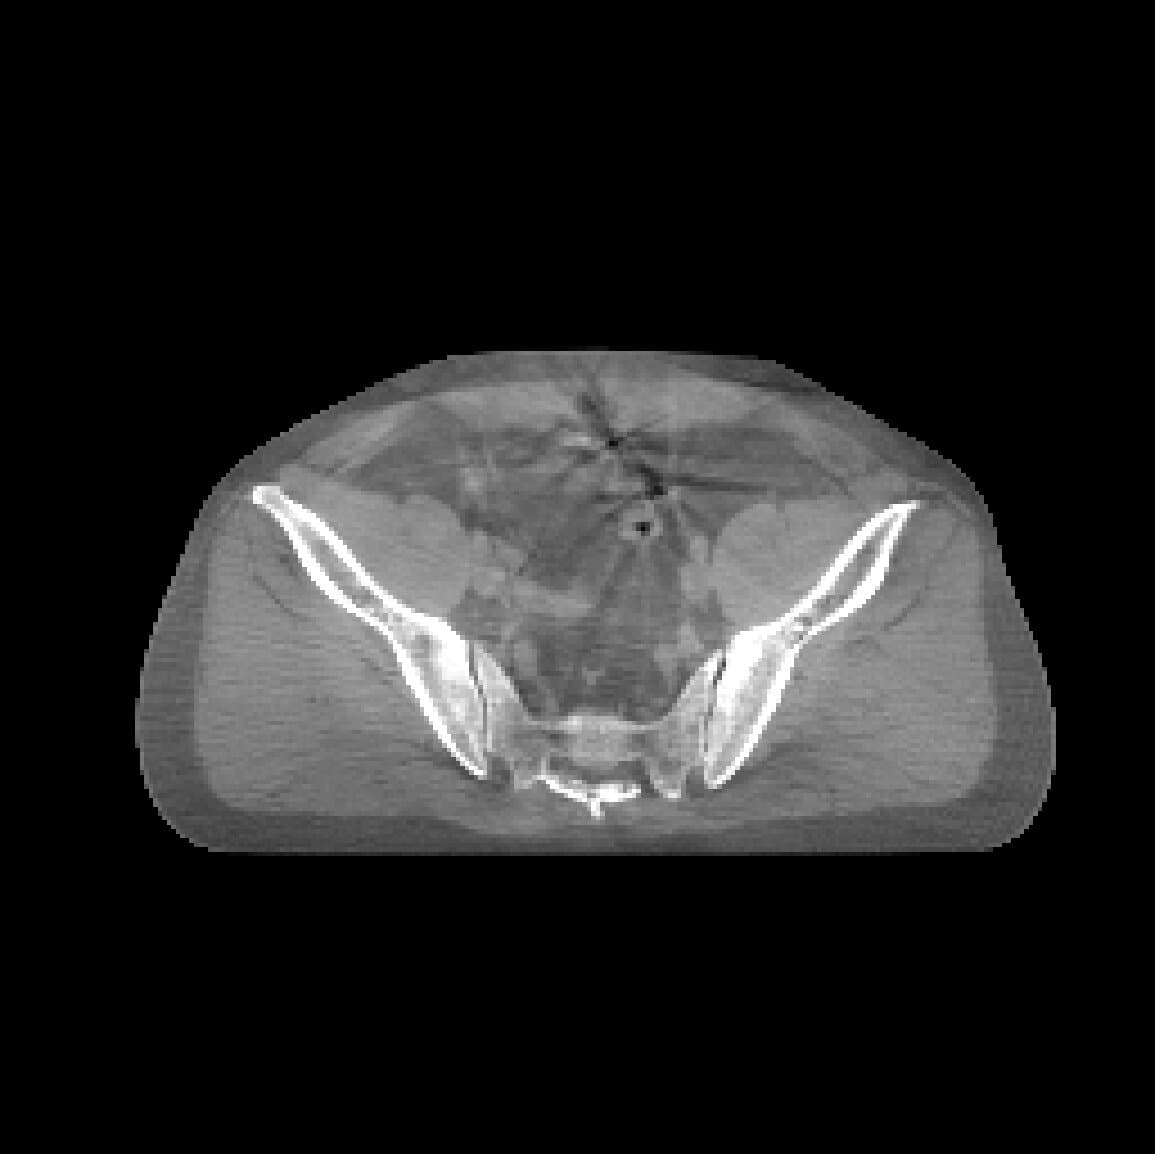

CycleDPM is a dual-stage diffusion model framework for anatomy-preserving CBCT-to-CT image synthesis, designed for adaptive radiation therapy. CBCT images suffer from noise and scatter artifacts that degrade their clinical utility, and CycleDPM corrects these artifacts to synthesize high-quality CT images directly from CBCT scans.

The method achieves state-of-the-art quantitative results with MAE: 67 -> 46.9 [HU] and SSIM: 0.845 -> 0.902, outperforming GAN-based baselines. The work was presented at ICNGC 2025 and is currently being prepared for broader publication.

Compare the original CBCT slice with the synthesized CT output using a draggable divider and a direct slider control.

Use the handle or the range control to compare CBCT and synthesized CT.